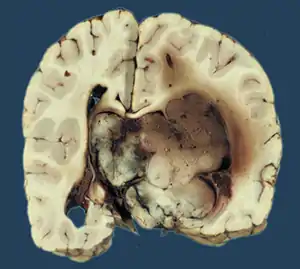

Choroid plexus papilloma

Choroid plexus papilloma, also known as papilloma of the choroid plexus, is a rare benign neuroepithelial intraventricular WHO grade I lesion found in the choroid plexus.[1] It leads to increased cerebrospinal fluid production, thus causing increased intracranial pressure and hydrocephalus.[2]

Choroid plexus papilloma occurs in the lateral ventricles of children and in the fourth ventricle of adults. This is unlike most other pediatric tumors and adult tumors, in which the locations of the tumors is reversed. In children, brain tumors are usually found in the infratentorial region and in adults, brain tumors are usually found in the supratentorial space. The relationship is reversed for choroid plexus papillomas.

The tumor is neuroectodermal in origin and similar in structure to a normal choroid plexus. They may be created by epithelial cells of the choroid plexus.